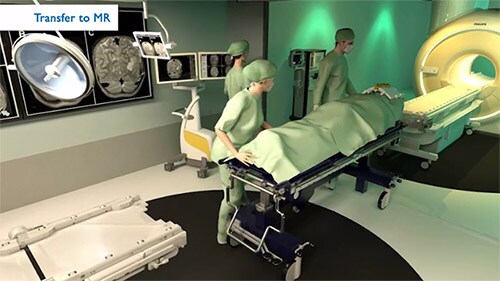

The heart of the latest Philips MR-OR intra-operative neurosurgery solution is a 1.5T or 3.0T Ingenia MR system. It occupies a normal diagnostic MR room that can be directly connected to one or two operating rooms. During a tumor resection procedure, the patient can be moved smoothly, straight to the MR scanner just a few feet away. Transfer times are short, and the MR images can be acquired quickly. This helps the surgical team to make critical decisions right away. If needed, several intra-operative MR exams can be done during the same surgery. MR-OR provides surgeons with up-to-date information on the outcomes of the procedure to share with patients and their families immediately after surgery, and reduces the anxiety of waiting several days for the results to be available.

Watch the video: This short video illustrates the workflow in a triple-room MR-OR.

The Philips MR-OR solution places the MR system in its own room, separated from the OR by sliding doors to maintain the OR sterility measures. In addition to standard front docking, the Philips MR-OR solution also features a rear-docking capability. That means you can connect not just one, but two or more ORs to the MR room to increase equipment utilization. Each room is a separate entity that can be used fully independently. In between intra-operative procedures, the MR system can be used for normal diagnostic imaging.